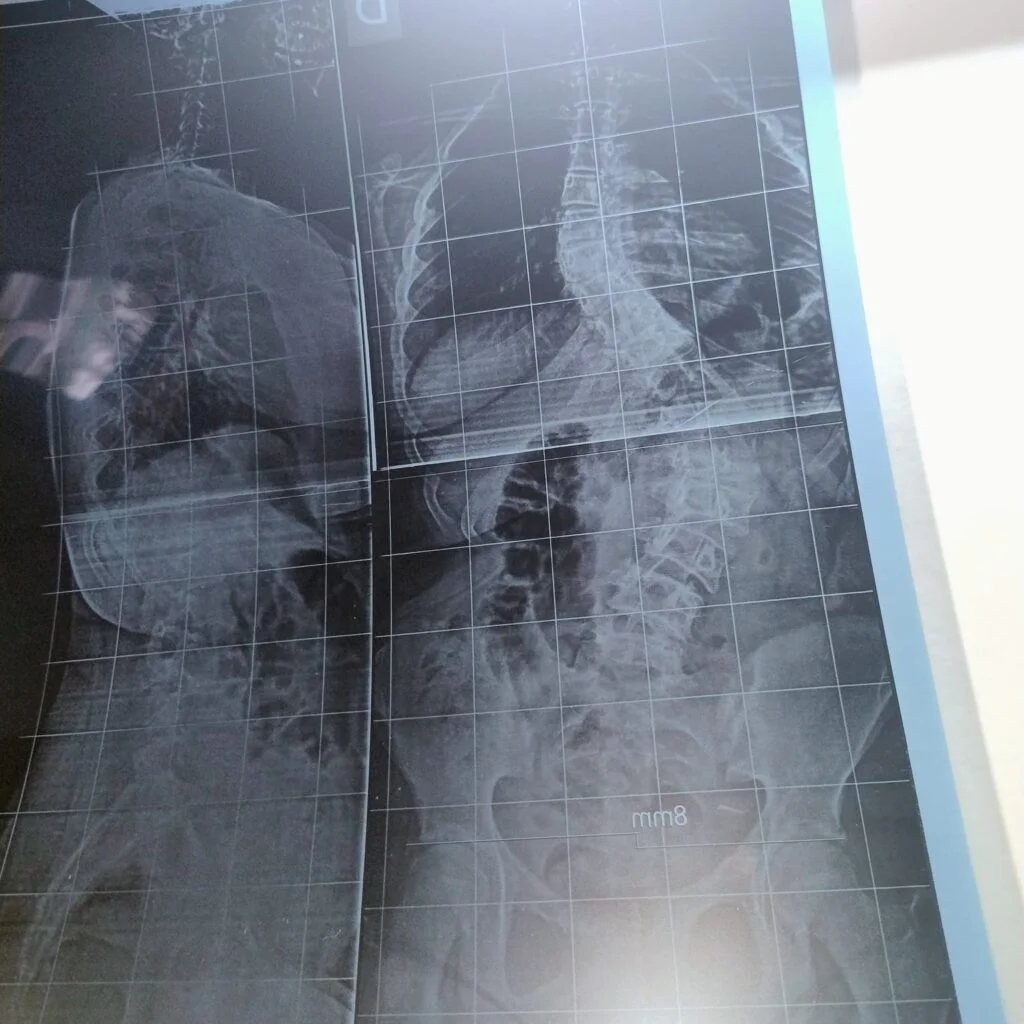

El caso de Alessia se agravó en los últimos meses. La curvatura de su columna alcanza los 80 grados y compromete gran parte de su estructura corporal. El diagnóstico, que comenzó a detectarse en la infancia, se intensificó con el crecimiento.

La familia advirtió que la operación debe realizarse antes de julio para evitar complicaciones mayores, que pueden afectar órganos vitales como el corazón y los pulmones.